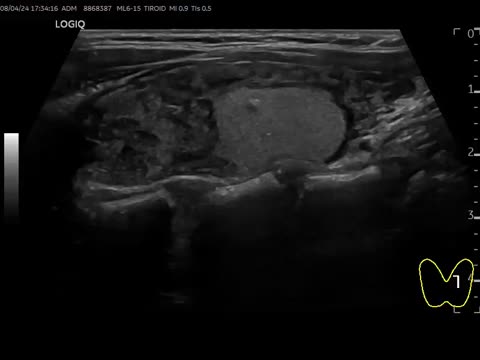

Espongiforme (0 puntos): contiene múltiples componentes microquísticos en su interior. Sugieren benignidad (video 1)

- •

Mixto (1 punto) (video 2)